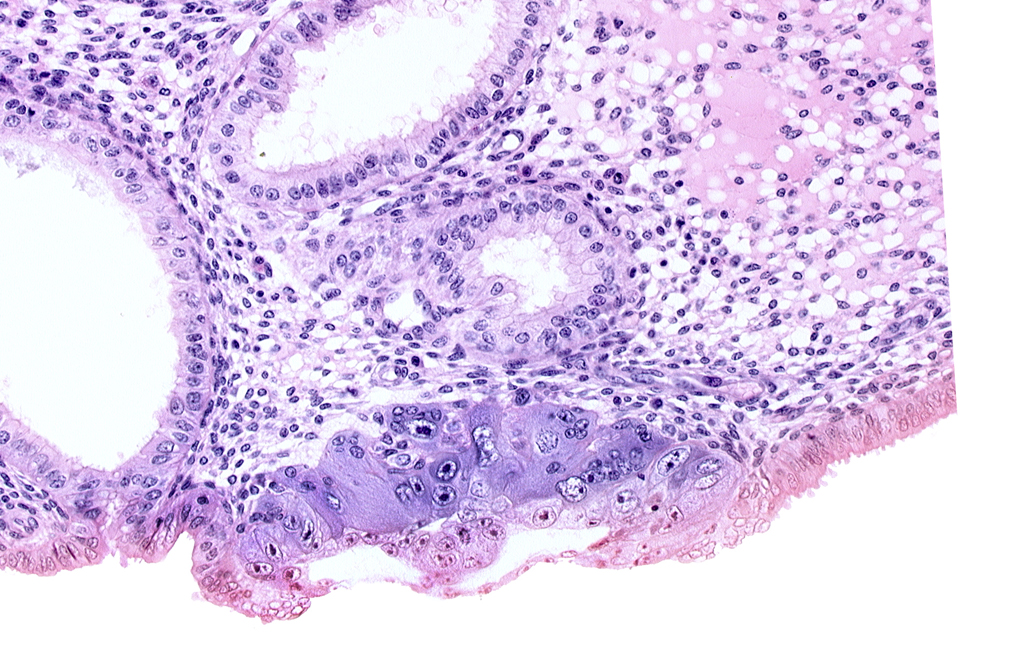

Carnegie Embryo #8020 | Location: 06-02-07

Keywords: amniotic cavity, blastocystic cavity (blastocoele), cytotrophoblast, edematous endometrial stroma (decidua), endometrial epithelium, endometrial gland, endometrial sinusoid, lumen of endometrial gland, solid syncytiotrophoblast

Source: The Virtual Human Embryo.